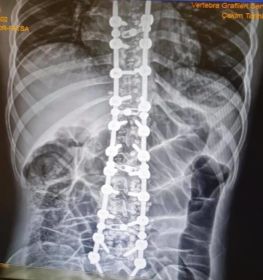

Omurga eğriliği yaşan insanlarda eğer eğrilik 40 dereceyi aşmış ise cerrahi operasyon ile tadavi edilir. Bu şekilde bir tedavi çok riskli ve zordur. Ardından ise mutlaka fizik tedavi ek olarak da korse tedavisi uygulanmalıdır.